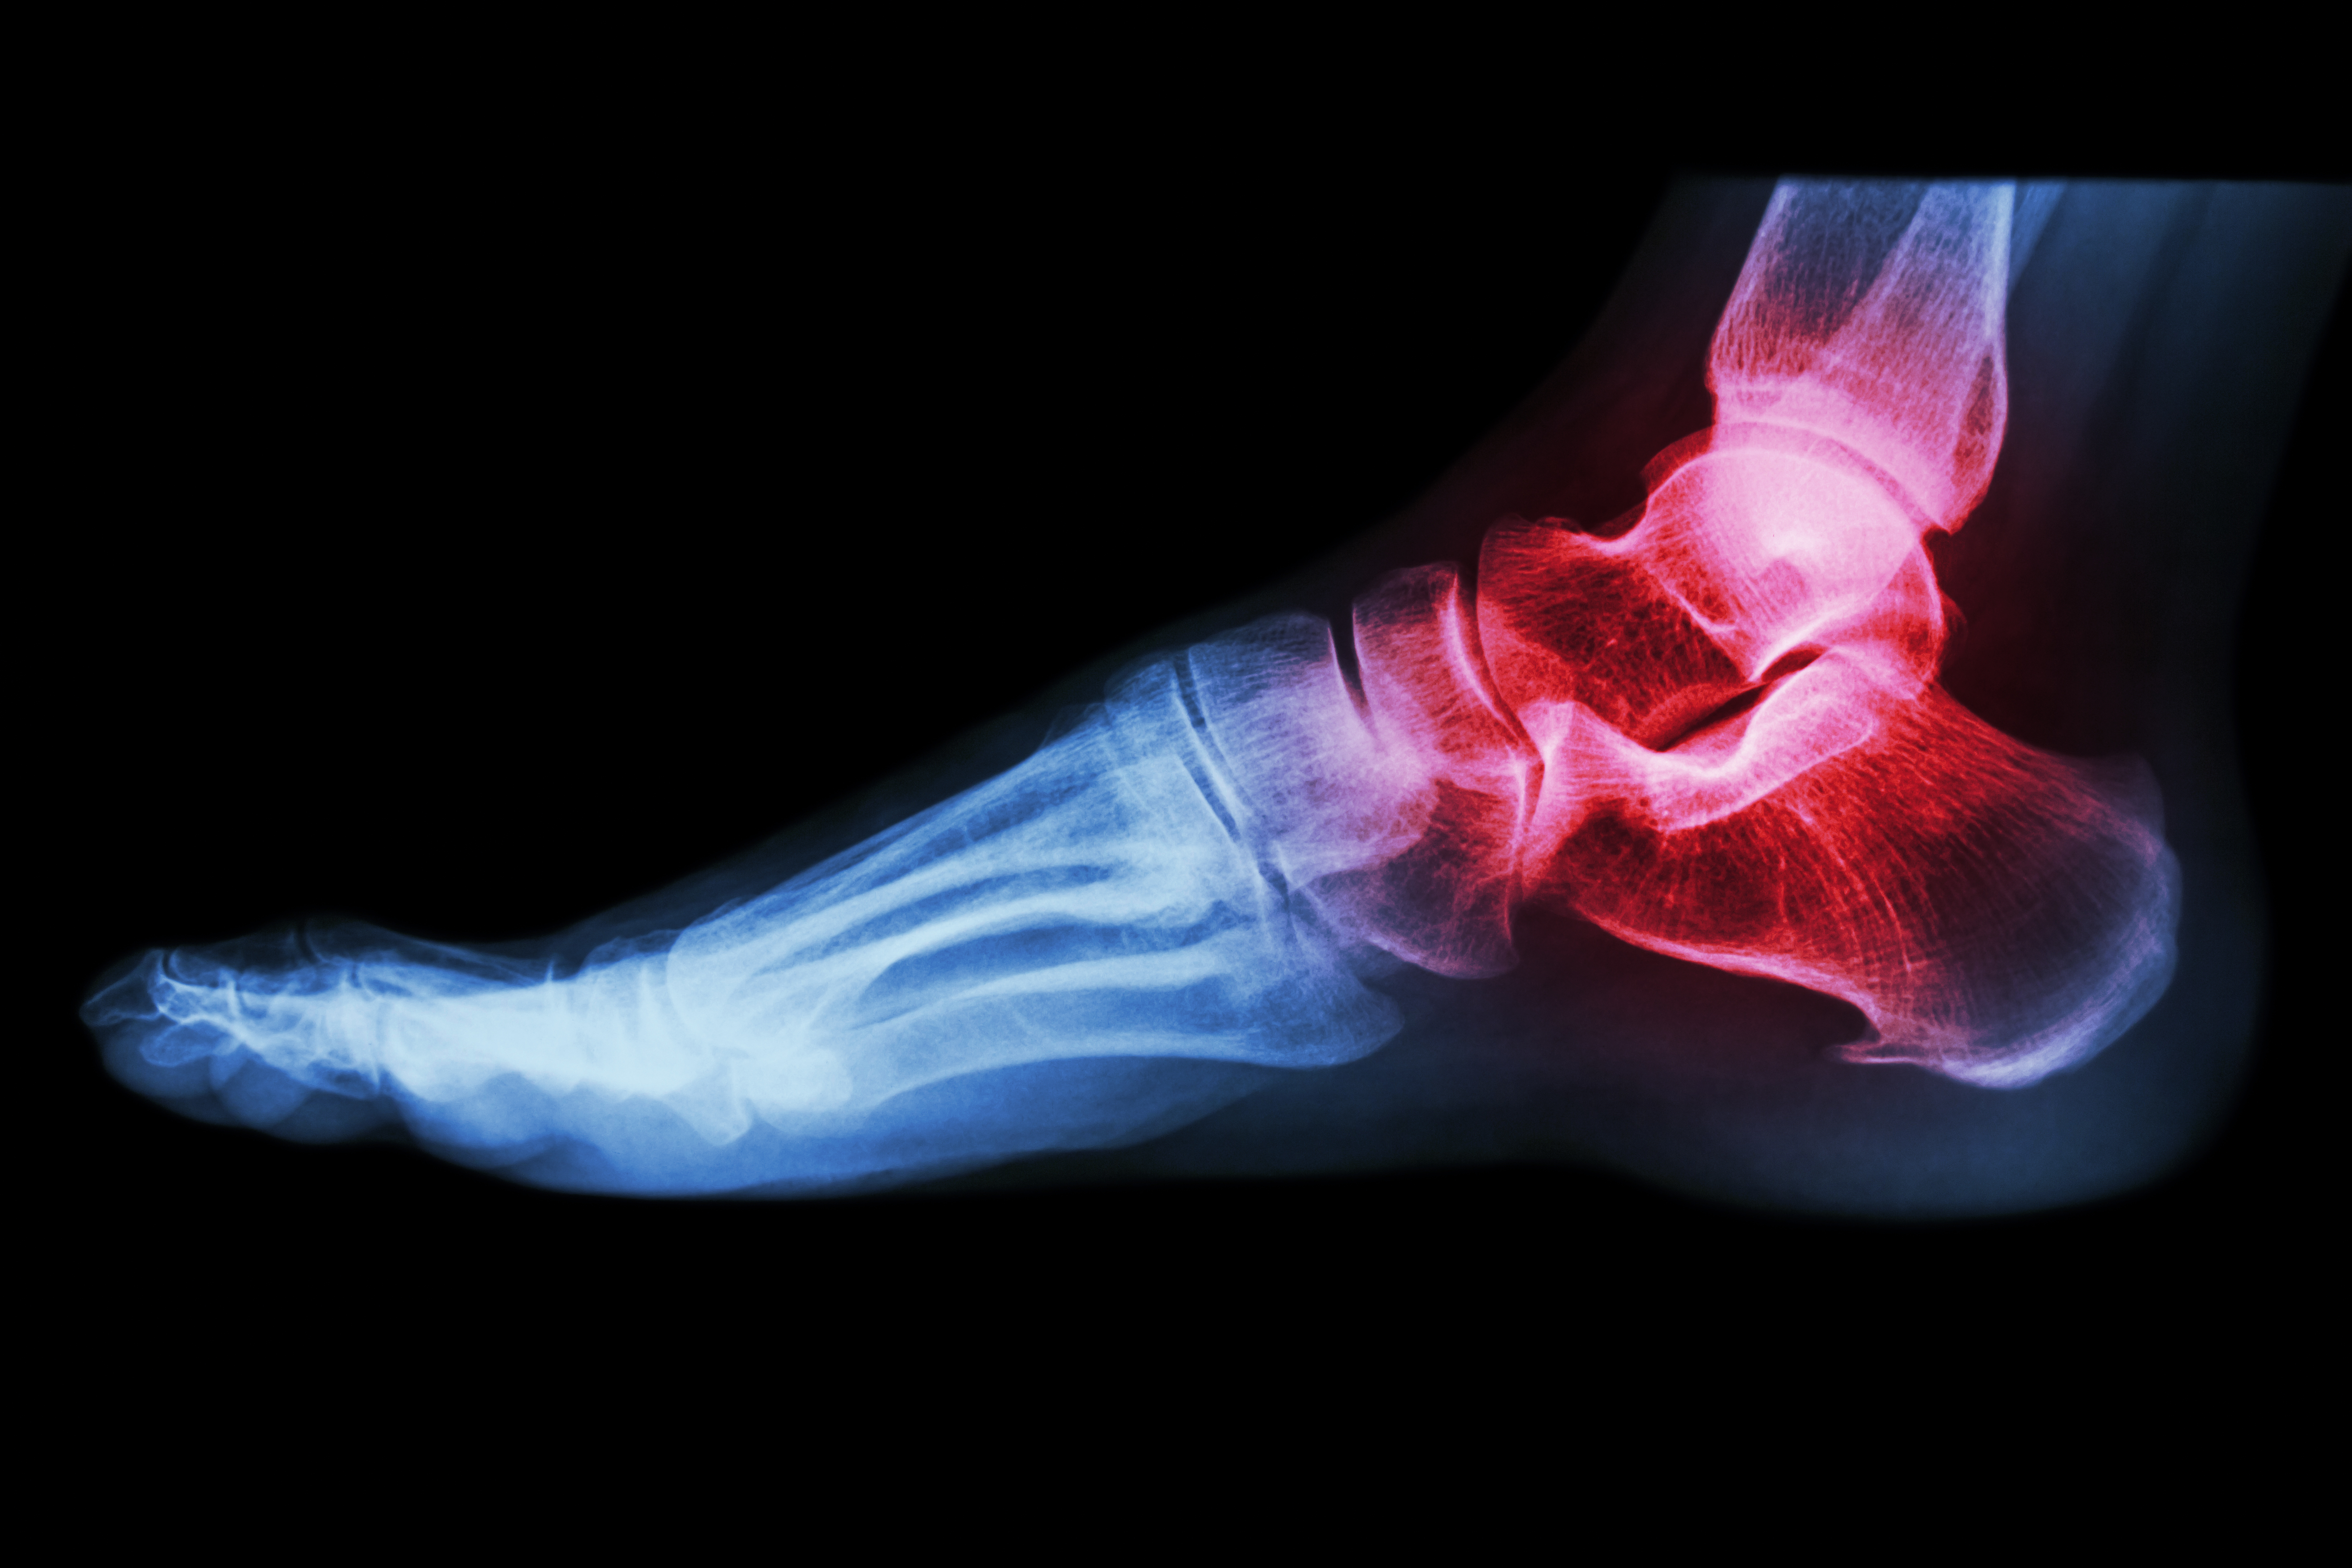

- Fish oil: If you have inflammatory arthritis (red, swollen joints, as in rheumatoid arthritis) add fish oil (1 teaspoon or 3 capsules 2-3 times a day for 6 weeks, then once a day).